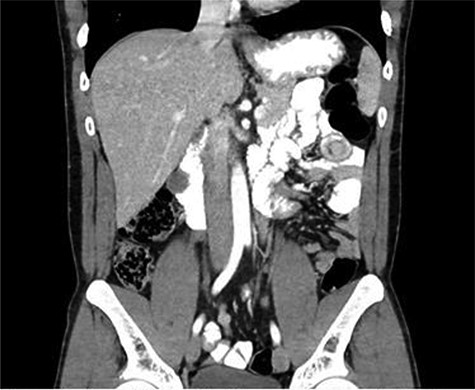

CT scan diagnosed 100% of the cases and all cases were reported as jejunojejunal (JJ) intussusception (Figs 1, 2). CT scan identified two patients having more than one intussuscepted segment. None of the patients were found to have lead points on imaging.

A 30-year-old male with CT scan with target sign in left upper quadrant suggesting JJ intussusception